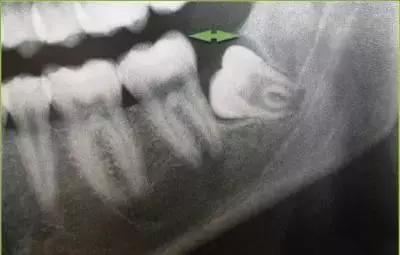

相信大家都知道,由于智齿萌出得较晚,所以不少人的智齿都会错位萌生或者萌生不全,再加上刷牙难刷到如此深入的位置,智齿处的食物嵌塞就会比较严重,往往容易导致发炎,发炎的时候可出现牙痛,严重时还可导致低烧。

这里不得不提到的则是:智齿萌出不全特别容易引起智齿冠周炎,这种炎症常发生于下颌处,早期时患者可出咽喉旁软组织胀痛、咀嚼与吞咽都十分困难,甚至不能开口说话,病情加重后,可引起相应颊肿胀,局部有自发性跳痛或耳颞部出现反射痛。